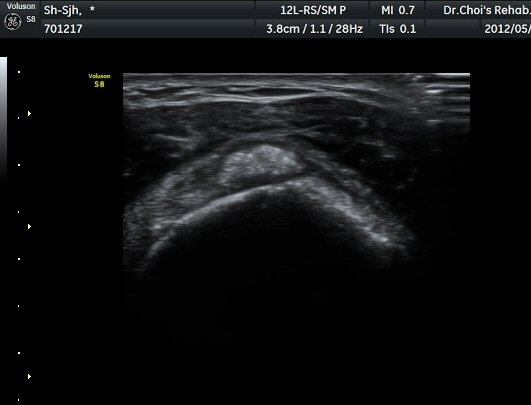

Á߸³»óÅ ¾î±ú ¾Õ Ⱦ´Ü¸é°Ë»ç¿¡¼­ À̺ειڱ٠ÁÖÀ§¿¡ ¼ö¾×Àú·ù°¡ °üÂûµÇ°í(»çÁø 1) ÆÄ¿öµµÇ÷¯